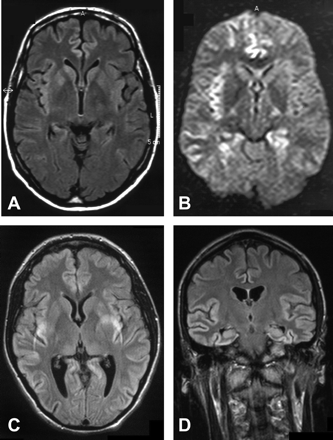

SPECT /宠物。

9名患者接受了核诊断测试的SPECT(5例)和宠物等(1例)(表e 1,上可用首页网站www.首页neurology.org)。在核磁共振成像中,颞叶是最常受影响(6例),其次是顶叶(5例)以及额叶和枕叶(4例)。

在疾病的进一步的课程他发达的视觉障碍,眩晕,手和脚的麻木。他取得了14 30分的细微精神状态检查。SPECT显示左脑灌注不足(图2)。脑电图显示在左额颞叶瓣的关注。病人发展幼稚的行为和言论的损失。一年后开始他的运动不能的哑,显示增加肌肉和肌阵挛。他仍然在这种状态下1年和后死亡疾病的2年。

在核磁共振,颞叶也经常在SPECT和PET的影响。

最早的SPECT发现我们的一个病人是一个低灌注的颞叶发病后3个月。患者检查后5个月或之后显示广泛的皮层的参与。然而,正如之前提到的其他作者,没有具体的损伤模式到目前为止已经发现了库贾氏症。24日,25